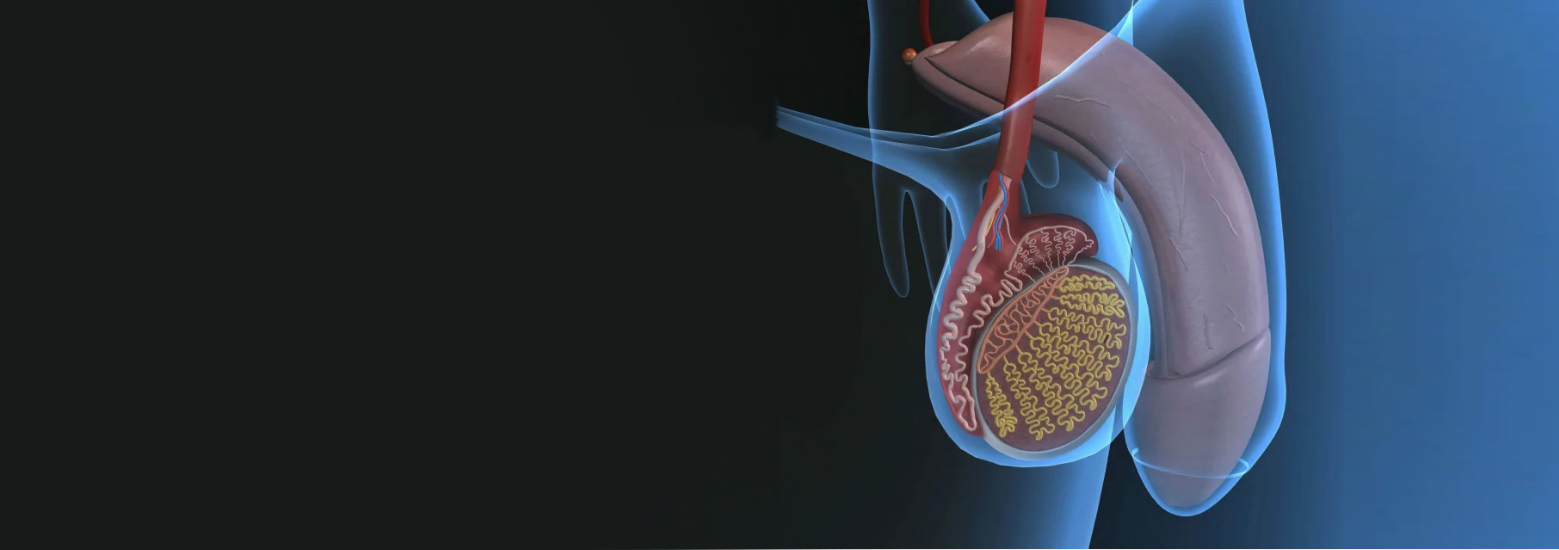

мболизация яичковой

Эмболизация яичковой 115 фото